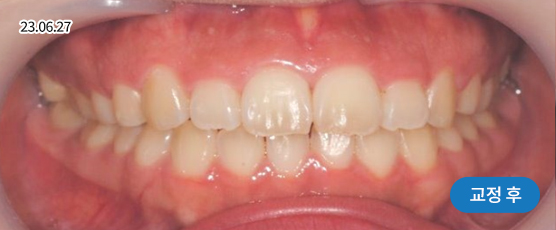

덧니교정 Solution

덧니는 악궁 크기, 얼굴형, 골격 등을 고려해 발치, 비발치를 현명하게 판단하여 치료합니다.

치아가 정렬될 공간을 확보하기 위해, 경우에 따라 소구치(작은 어금니)를 발치할 수 있습니다.

* 본 사진은 동일 조건에서 촬영되었으며, 환자 본인의 동의를 얻어 게재되었습니다.